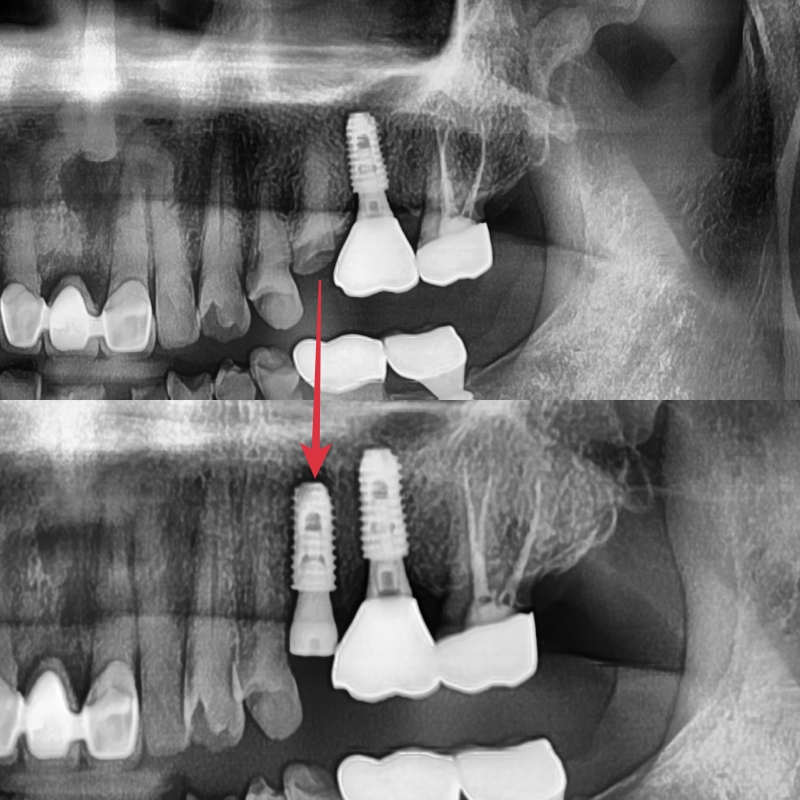

해당 치아는 발치 후 임플란트를 진행하였고, 약 3개월 정도 주변골과 골유착이 진행될 때까지 기다렸습니다.

임플란트의 보철만 제작하기에는 몇가지 문제점이 있었습니다

첫 번째, 공간이 너무 부족하고,

두 번째, 반대편의 대합 되는 치아들이 이미 파절, 마모로 인한 치아 형태의 변형으로 제대로 된 교합을 형성해 줄 수 없었습니다.

세 번째, 임플란트가 완성되면 대합 되는 치아는 과한 교합력으로 인한 향후 파절 가능성이 높습니다.

이런 이유들로 장기적으로 보았을 때 제대로 된 교합을 형성해 주기 위해 주변 치아들의 보철 치료가 필요했고, 환자분께 상기 이유에 대해 자세히 설명드렸고, 환자분께서는 치료에 대한 필요성에 대해 이해하시고 보철치료를 같이 진행하게 되었습니다.

치료 후 엑스레이 사진입니다

하얀색으로 보이는 부분이 보철물로 인해 회복된 치아입니다.

신경치료 없이 치아의 생활력을 유지한 채 치료는 마무리되었습니다.

정기적으로 검사를 하며 지내시면 기존 파절 상태보다 치아의 수명은 늘어날 것입니다.